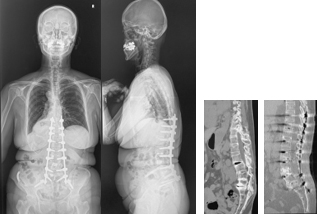

重度脊柱変形に対する矯正固定術

さまざまなお体の病気に伴い、せぼねが重度に変形を起こし息切れなどの症状が出る場合があります。

これらの患者様に対しては状況に応じて、せぼねを矯正固定する場合があります。小児科やリハビリテーション科と相談しながら手術時間や入院期間を検討していきます。